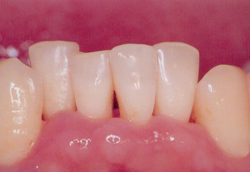

전

치석과 염증이 제거되며 스켈링 전보다 다소 잇몸이 내려가고 치간이 넓어진 느낌에 놀라실 수도 있습니다. 하지만 이는 치석과 염증이 있던 공간이 비워지고 잇몸이 원래의 잇몸뼈 부근으로 자리를 잡으며 생기는 변화입니다.

치석과 염증 등으로 잇몸과 잇몸뼈의 공간이 4mm가량이나 벌어져있던 치료 전과 비교했을 때 치료 후에는 잇몸과 잇몸뼈의 공간이 2~3mm를 유지할 수 있게 됩니다.